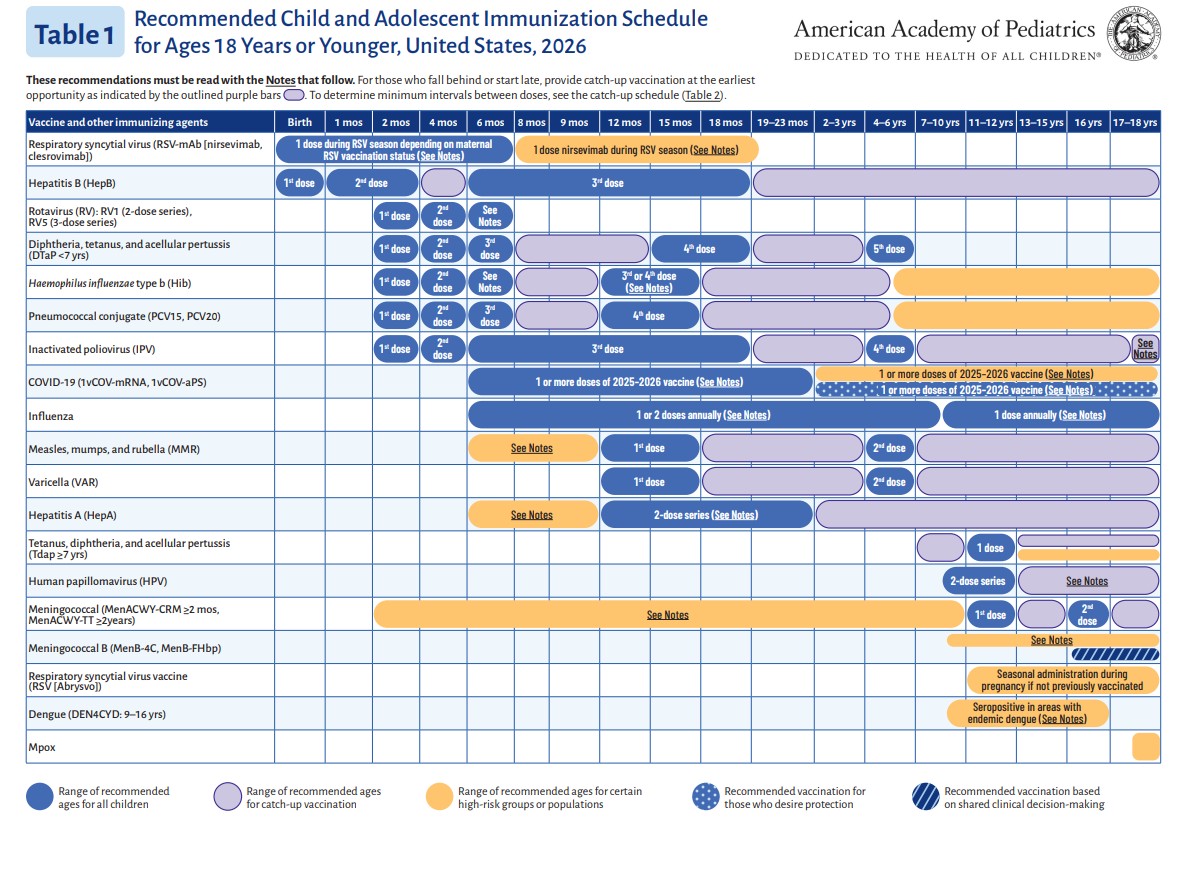

p 2